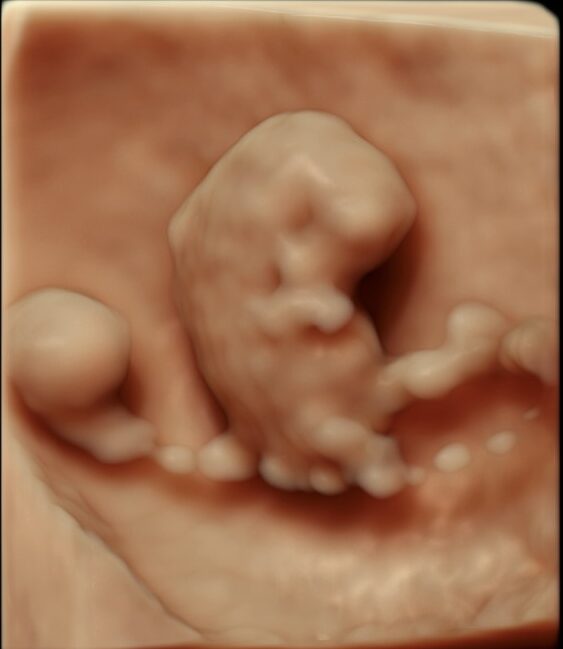

条件が良ければ、こんな感じで赤ちゃんをみることができます(写真は、お母さんにホームページに載せることを許可していただいています)。

赤ちゃんの協力も必要なので、残念ながらいつもこのようにみえるわけではありまんが、

一番はじめのエコー画像は妊娠9週のものですが、この時期ですでに頭も手も足もしっかりできています。